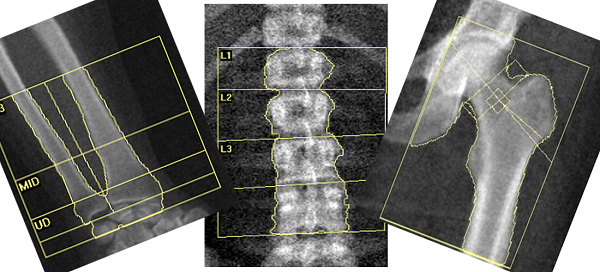

جمشیدی بیان داشت: همه افراد بالای 65 سال باید سنجش تراکم استخوان انجام دهند و این مسئله برای بیمارانی که از داروهای خاص مانند داروهای ضدانعقادی، ضد تشنج، ضد شیمیدرمانی و داروهای پرکاری و کم کاری تیروئید، دیابت، مصرف میکنند باید زودتر از سن 65 سال مورد بررسی و معاینه قرار گیرند.